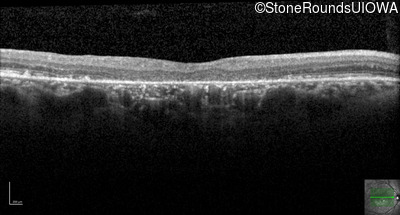

Optical Coherence Tomography - Right - 20/200

Exemplar / OCT Stack